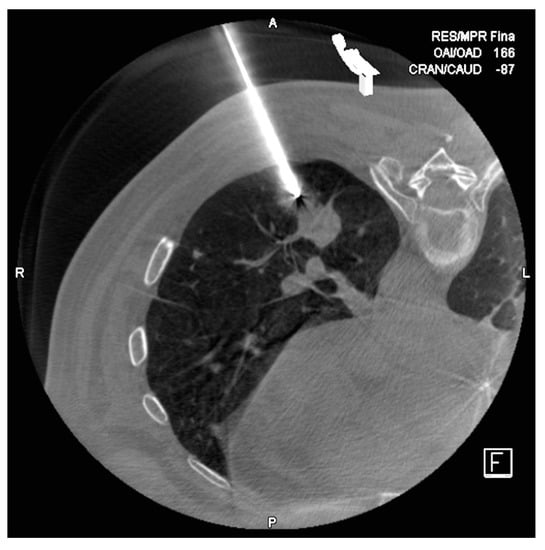

Cone-Beam CT-Guided Lung Biopsies: Results in 94 Patients

2. Materials and Methods